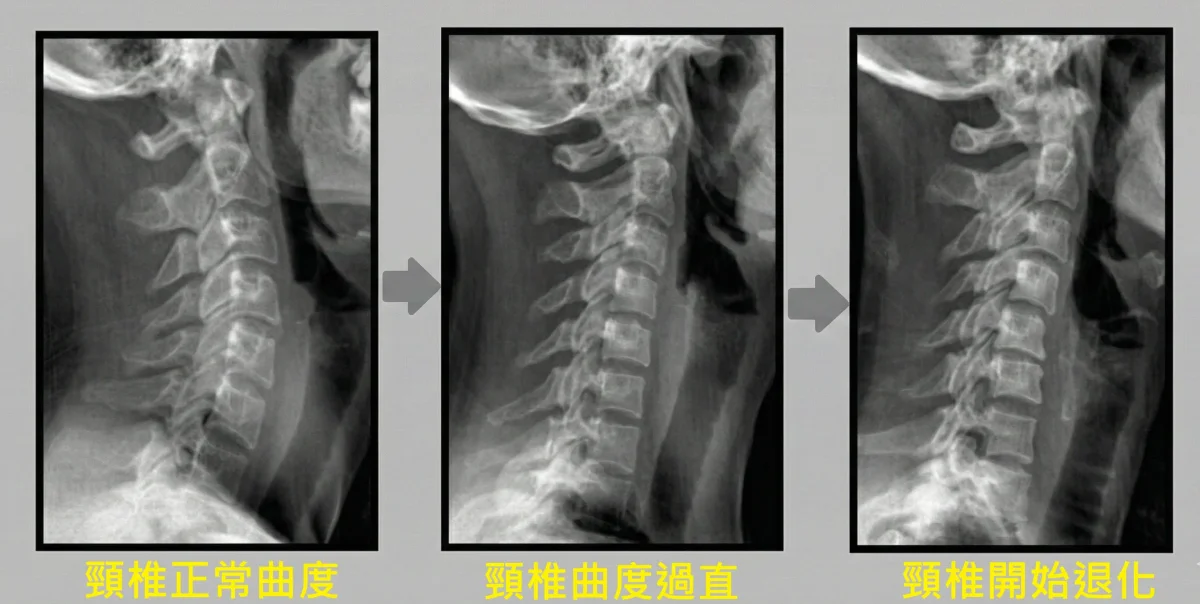

🔍 X光下的發現:頸椎曲度消失及退化

上交叉症候群的患者,X光可以發現倒C的曲度 不見了,變成I型的脊椎,漸漸地開始長出骨刺或椎間盤突出。